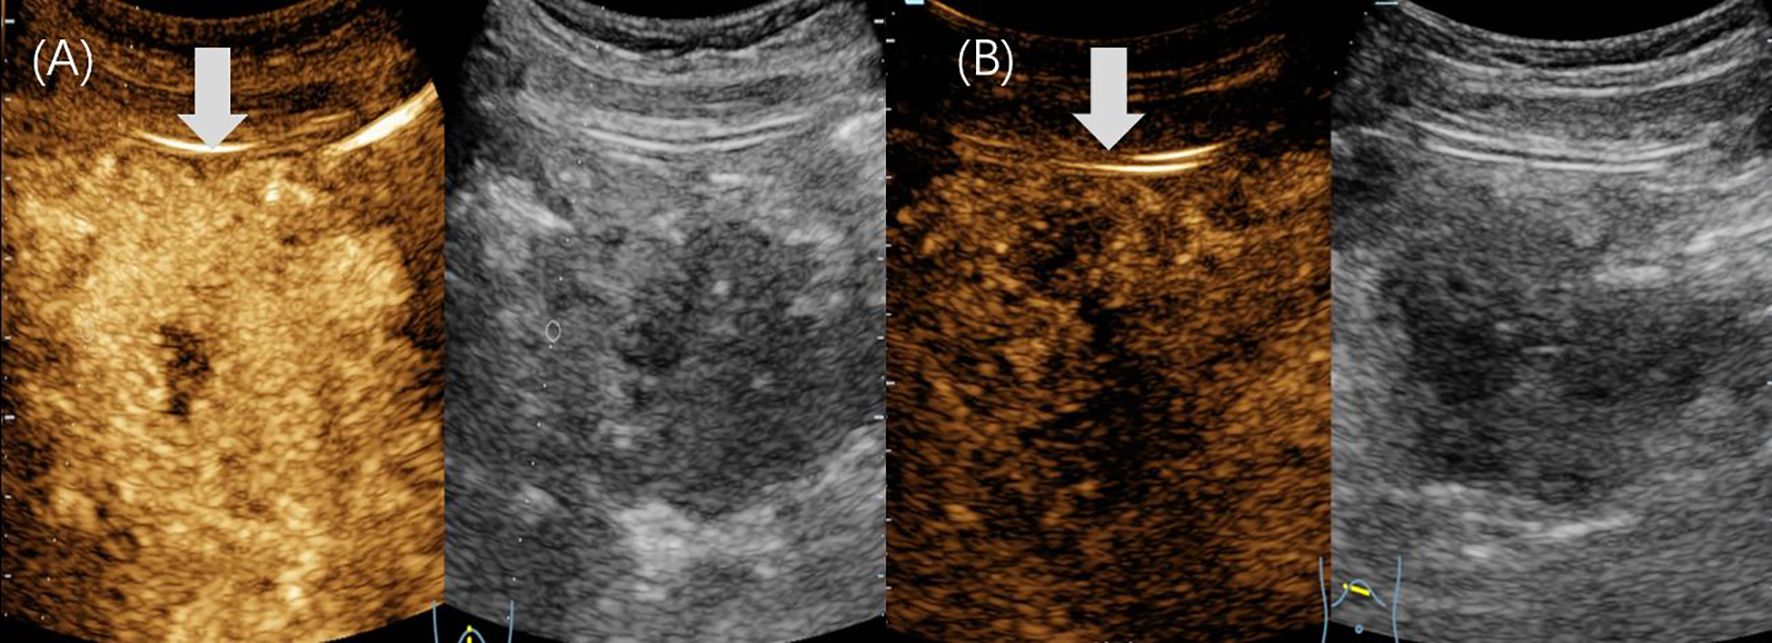

Pancreatoblastoma (PB) is a rare malignant neoplasm of the pancreas, primarily affecting children. While some reports have described the imaging characteristics of PB, detailed descriptions of its ultrasound (US) and contrast-enhanced ultrasound (CEUS) features in children are limited. We reported two cases of PB admitted to our hospital with detailed ultrasonographic features. The first case involved a 14-year-old girl who presented with intermittent, unexplained epigastric pain. CEUS revealed a hypoechoic mass with heterogeneous hyperenhancement in the pancreatic head. She underwent pancreaticoduodenectomy and remains disease-free to date. The second case was a 4-year-old boy with a palpable, unexplained mass in the right upper abdomen. US identified a well-defined, heterogeneous mass in the epigastric region with internal point-like hyperechoic areas. The intraoperative US showed portal vein cancer thrombus. He underwent tumor resection along with reconstruction of the portal and superior mesenteric veins. He subsequently received chemotherapy and remained disease-free to date.